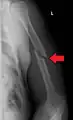

A transverse fracture of the humerus shaft

A spiral fracture of the distal one-third of the humerus shaft- A displaced supracondylar fracture in a child